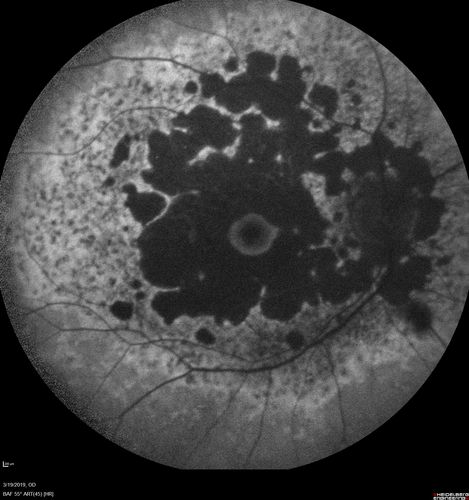

Concentric Geographic Atrophy

76 year old man Gradual vision loss

20/32 OD; 20/40 OS

No medicines, Non-smoker

Working and Driving